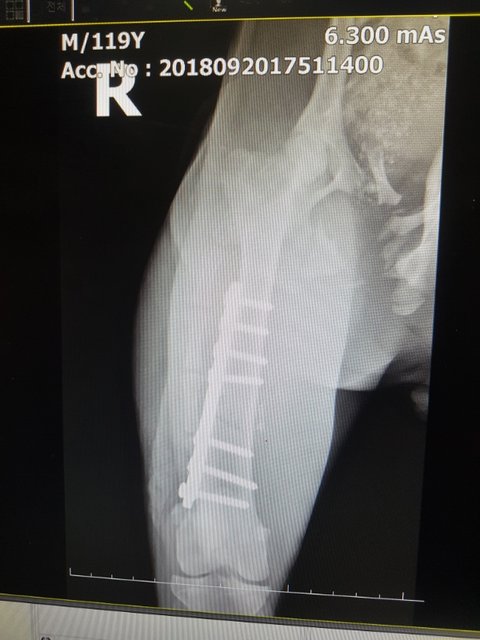

수술도 아주 잘되었다고 합니다.